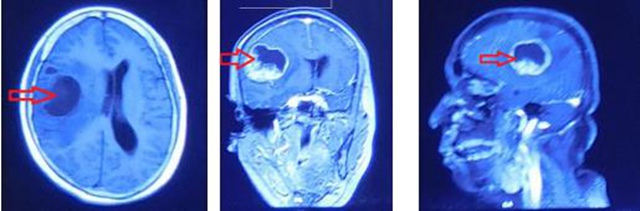

家住冯井镇何庄村的李某某,因头痛在某医院诊断为“脑梗死”并对症处理,效果欠佳,然后到上海某三级医院进行治疗,进行头颅MR检查(红箭头所示分别为轴位、冠状位及矢状位)确诊为高级别胶质瘤,因有甲减病史,医院建议缓期进行手术治疗。